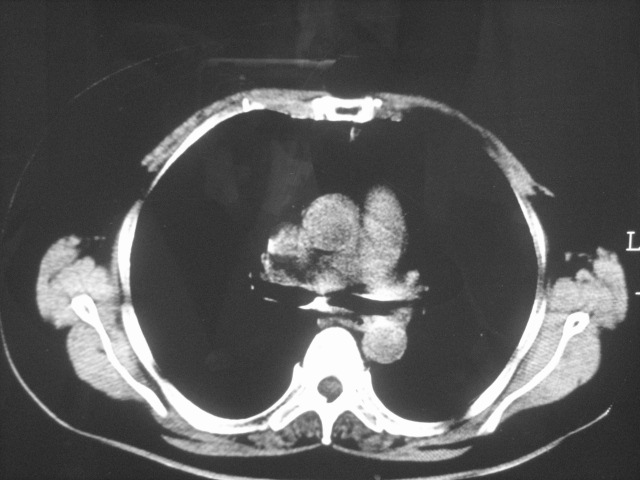

以下是引用清清楚楚在2007-8-28 7:13:00的发言:[br]右肺下叶可见斑片状高密度影,边缘模糊;右肺中叶内侧段及左肺舌段亦可见小斑片状模糊影。[br]考虑双肺感染,建议抗炎治疗后复查。

以下是引用天南地北在2007-8-27 23:49:00的发言:[br]右肺下叶可见斑片状高密度影,边缘模糊;右肺中叶内侧段及左肺舌段亦可见小斑片状模糊影。[br]考虑双肺感染,建议积极抗炎治疗后复查。

以下是引用难听在2007-8-28 13:17:00的发言:[br]右肺下叶背段支气管狭窄,是否可以考虑新生物伴阻塞性肺炎.请大家帮帮忙,这个病人是卫生局长的丈母娘.惹不起啊.